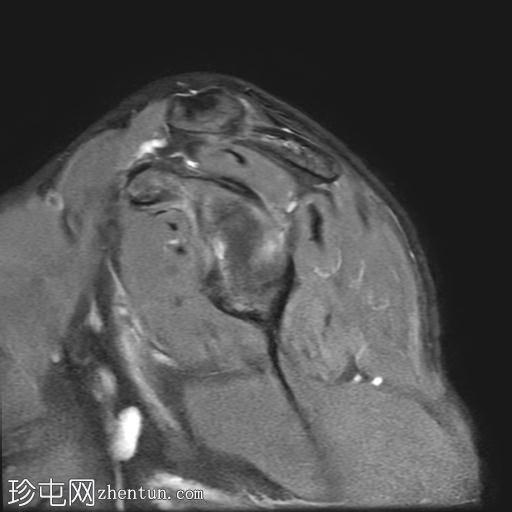

右肩外伤。

年龄:25岁

性别:男

MRI

冠状位

T2加权像

Bankart损伤伴前盂唇及下方骨髓水肿

Hill-Sachs缺损表现为骨性压陷,肱骨头后外侧及下方骨髓水肿/挫伤

冈上肌腱关键区纤维肌腱病

MRI结果符合肩关节前脱位伴Hill-Sachs缺损和Bankart损伤的

影像

学表现。